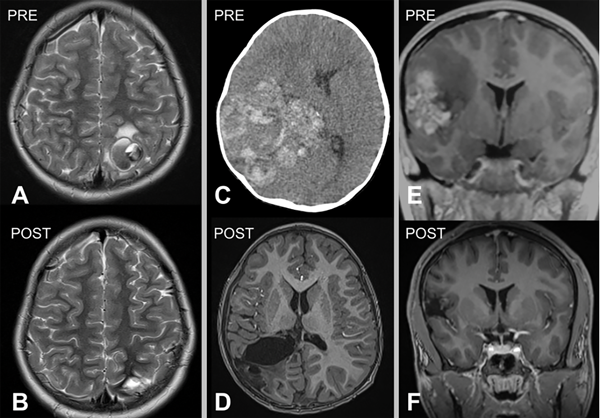

Figura 1. Tres casos de cavernomas cerebrales supratentoriales superficiales operados. A) y B) Imágenes prequirúrgicas y postquirúrgicas del paciente número 3: femenina de 7 años, que consulta por crisis parcial motora en miembro inferior derecho y crisis de ausencias. Secuencia SWI hipointensa correspondiente a restos hemáticos, secuencia T1 con contraste EV libre de lesión. C) y D) Imágenes pre y postquirúrgicas del paciente número 6: masculino de 2 años que es derivado por estatus convulsivo. TC de cerebro sin contraste que muestra extensa lesión parietotemporal derecha espontáneamente hiperdensa, con desvío de línea media y adelgazamiento de calota craneana homolateral. RM de cerebro con contraste EV, se observa cavidad porencefálica postoperatoria, recuperación de anatomía ventricular. E) y F) Imágenes pre y postquirúrgicas del paciente número 1: masculino de 12 años que consulta por crisis parciales simples motoras, que posteriormente generalizan. RM de cerebro con contraste EV que muestra lesión hiperintensa en región frontoopercular derecha. RM de cerebro con contraste EV postoperatoria, exéresis completa.

Las MC se localizan en el compartimento supratentorial entre el 60-90 %,1,3,9,17,24 y en nuestra serie fue del 61% (ver Figura 1). Acciarri y cols. encontraron predominio por el lado izquierdo en casos sintomáticos, mientras que nosotros no tuvimos predisposición por ningún lado.3 De nuestra serie, el 8% tuvo diagnóstico incidental, un porcentaje bajo e incluso menor a lo reportado por Bigi y cols. con un 14.2%.9